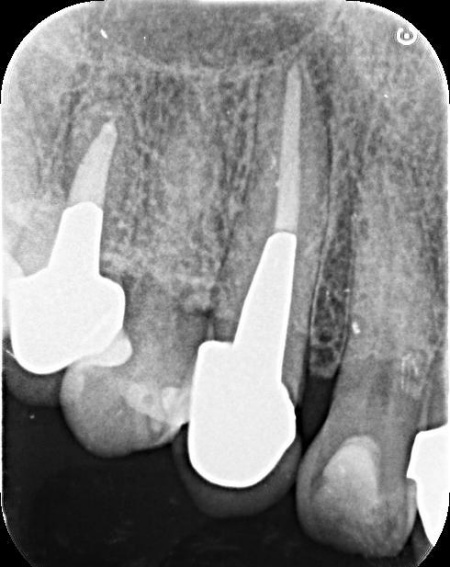

拝見したところ、右上の犬歯には被せ物が装着されていました。

被せ物が装着されていると、レントゲン検査で歯の内部の状態を正確に確認することは困難です。

そこで、原因を詳しく調べるため被せ物を慎重に取り外し歯の内部を確認したところ、歯根が縦方向に割れる「歯根の垂直破折」が認められました。

この状態になると、隙間から細菌が入り込んで周囲の骨や歯ぐきに感染が広がったり、接着や修復による温存が困難になったりします。